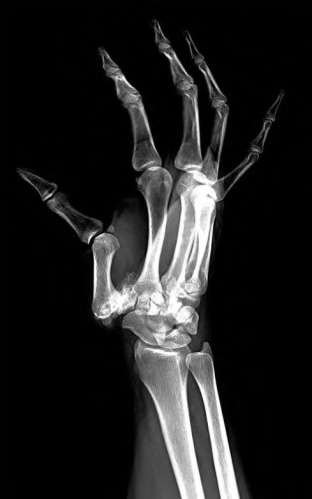

A 35-year-old woman reports wrist pain after a fall onto an outstretched hand. On exam, she has focal tenderness over the wrist snuffbox. A radiograph and CT image are shown in Figures A and B. What is the proper treatment of her injury?

Contrast enhanced MRA of the wrist is typically used to diagnose hypothenar hammer syndrome or other vascular abnormalities.